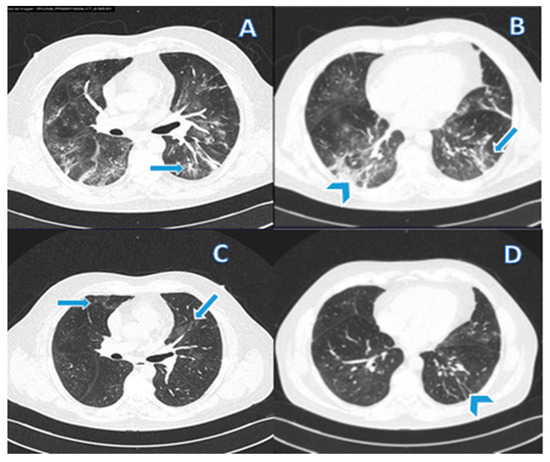

Pulmonary fibrosis was diagnosed in 31/149 (21%) patients based on a combination of tomographic findings, including parenchymal bands, irregular interfaces, a thick reticular pattern, and bronchiectasis confirmed by a pulmonologist. Figure 2 and Figure 3 shows computed tomography scans from patients without (Figure 2) or with (Figure 3) diagnosis of pulmonary fibrosis after a follow-up of six months from initial infection by SARS-CoV-2.

Figure 3.

(A,B) CT from a 56-year-old male patient in the active infection phase of COVID-19. (C,D) CT after six months of infection resolution. Typical findings of COVID-19 pneumonia and tomographic findings that support the diagnosis of pulmonary fibrosis are observed. (A) Vascular thickening (arrow) associated with an area of ground-glass opacity; (B) Subpleural parenchymal bands (arrows) and ground-glass opacity and consolidation (arrowheads); (C) Absorption of most of the affected areas leaving some lesions in ground glass; and (D) Fibrous lesions that represent residual organizing pneumonia.